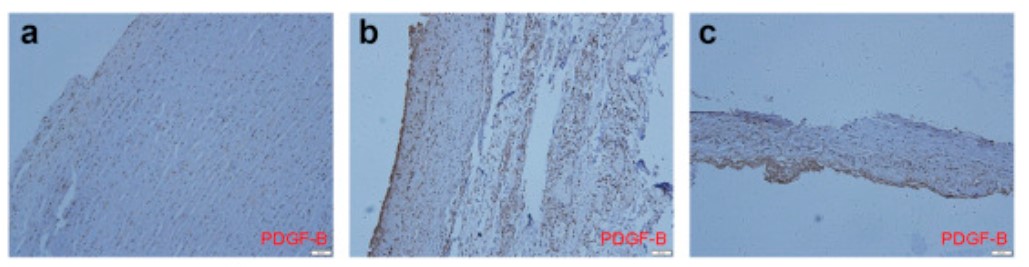

Thoracic aortic dissection (TAD) is a serious condition requiring urgent treatment to avoid catastrophic consequences. The inflammatory response is involved in the occurrence and development of TAD. This study aimed to determine whether expression of PDGF-B (a subunit of PDGF-BB) was increased in TAD patients. Full-thickness ascending aorta wall specimens from TAD patients (n = 15) and control patients (n = 10) were examined for expression of PDGF-B and its receptor (PDGFRB) and in terms of morphology, inflammation, and fibrosis. An increase in elastic fragments in the aorta wall might be responsible for inducing the activation and migration of macrophages to injured sites, leading to elevated expression of PDGF-B.

Fig1. Expression of platelet-derived growth factor B (PDGF-B) in ascending aorta wall.